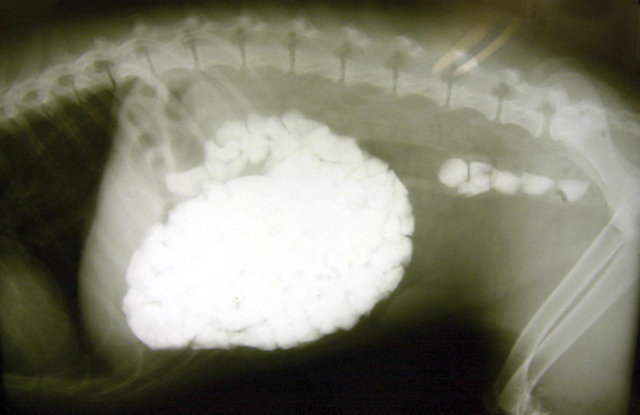

"Özellikle havaalanlarındaki girişlerde iki tür cihazı da görebiliriz. Eşyaların geçirildiği X-Ray cihazında X ışınları kullanılarak görüntüleme yapılır. Çantaların içinde ne olduğu X ışınları ile görüntülenir. Burada uygulanan X ışınlarının eşyalara bir zararı yoktur, birikmez, eşyalarda radyasyon kirliliği yapmaz. Bu cihazların çevresi X ışınlarının insanlara zarar vermemesi için kurşun paravanlarla kaplıdır."